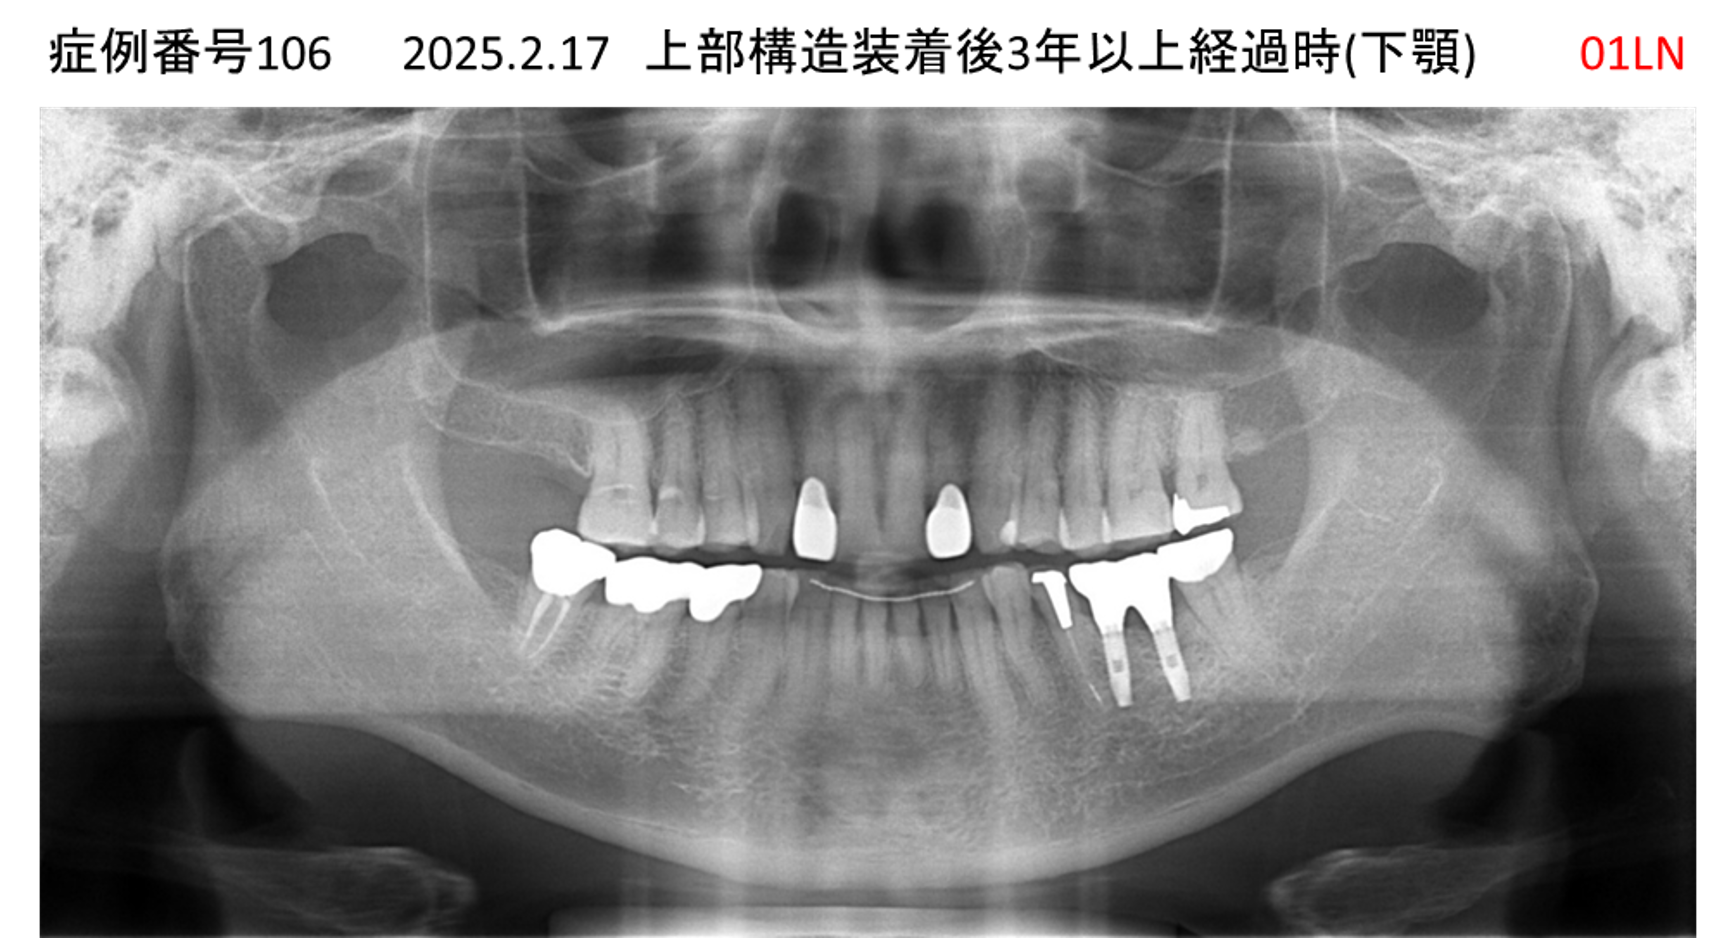

奥歯で噛めない患者様のインプラント症例

| 治療名称 |

インプラント |

| 治療費用 |

150万円+税 |

| 治療期間 |

3か月 |

| 患者さんの症状(主訴) |

奥歯で噛めない。食事がとれない。 |

| 治療内容 |

| 治療結果 |

食事に困らない。何でも食べられる。 |

| 治療の注意点(リスク/副作用) |

インプラントが壊れたら再治療が必要 |